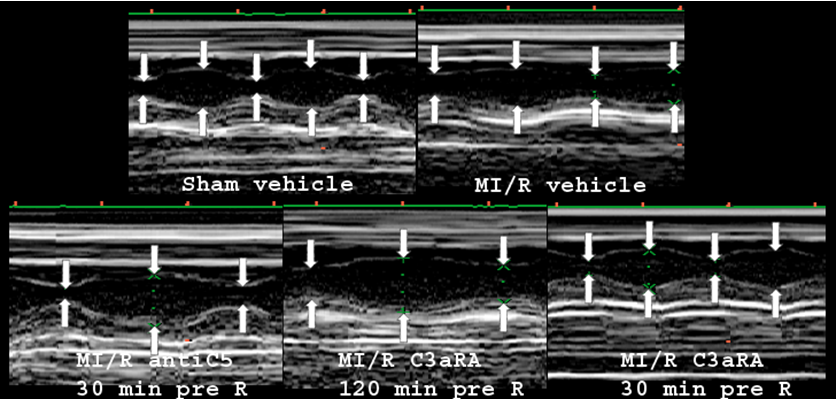

Previous work from our laboratory has shown that myocardial damage via infarct analysis is directly correlated with loss of left ventricular function as measured by echocardiography [5]. Therefore, in the present study, echocardiography measurements were used to assess cardiac function. Echocardiography was performed 4 hr after reperfusion using a Philips Sonos 5500 (Philips Medical Systems, Bothell, WA, USA) with a 7–12 MHz animal transducer (Agilent Technologies, Santa Clara, CA, USA), as we described [5], [14], [29]. Ejection fraction (EF) was calculated by left ventricular M-mode measurements and via long axis length and short axis area measurements of the left ventricle (LV) [30], [31], [32]. For EF, only M-mode data are presented, as both methods of EF measurements produced identical results.

Following 30 min of ischemia and 4 hr of reperfusion, a significant decrease in left ventricular ejection fraction (EF) in non-treated WT mice compared to sham-operated animals was observed (Figure 3 [Fig. 3] and Figure 4 [Fig. 4]). EF before MI/R was comparable to sham operated animals (data not shown). Mice treated with C5 monoclonal antibody 30 min prior to reperfusion were significantly protected from loss of myocardial function following MI/R compared to non-treated mice (Figure 3 [Fig. 3] and Figure 4 [Fig. 4]), suggesting a significant role of C5 in MI/R injury. The C3aRA is known to induce neutropenia that resolves within 120 min while its C3a receptor antagonism is still active [27]. MI/R in mice treated 120 min prior to reperfusion, when the neutropenia had resolved, but C3aRA was still active, induced a significant decrease in EF compared to sham-operated mice. In contrast, mice treated with the C3aRA 30 min prior to reperfusion were significantly protected from loss of myocardial function following MI/R, compared to sham-operated mice.